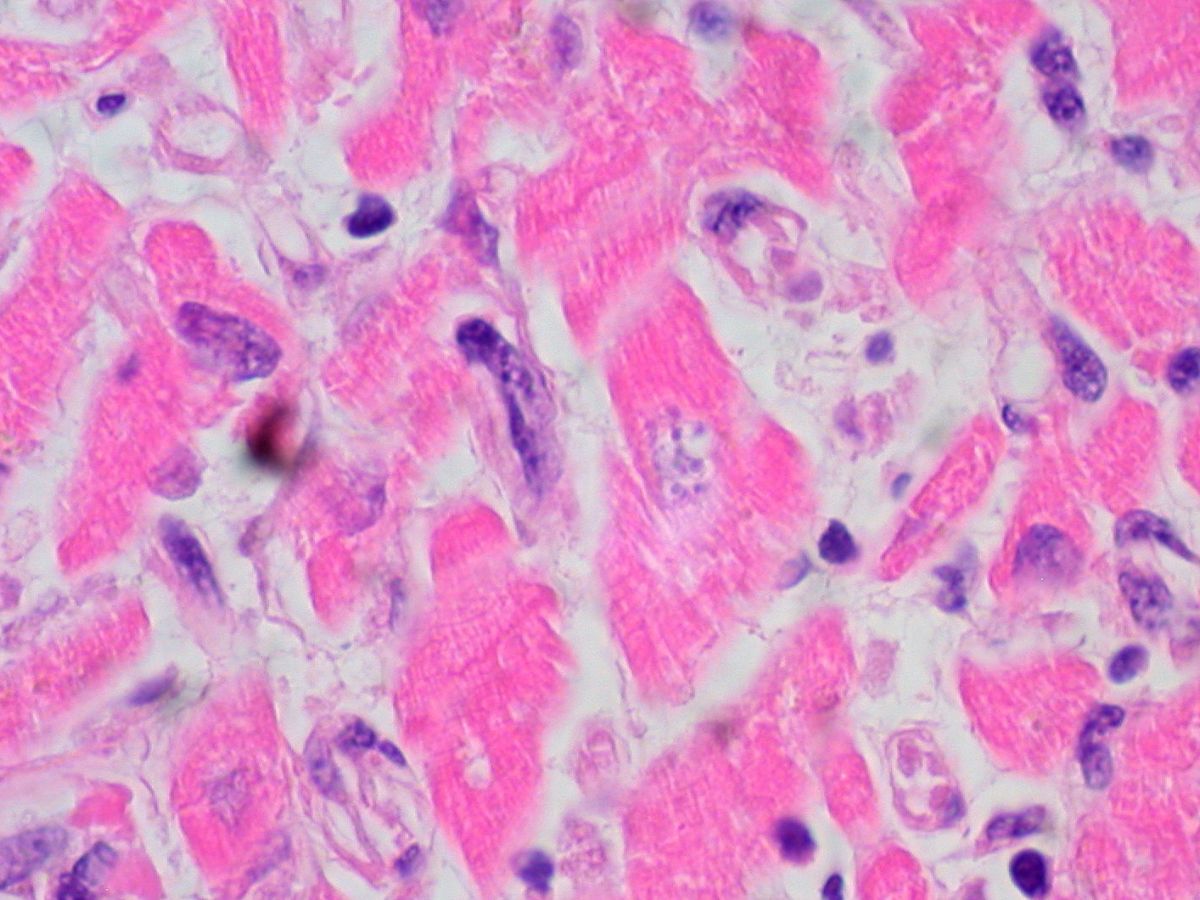

La enfermedad de Chagas afecta a más de 7 millones de personas en el mundo. Está causada por el parásito Trypanosoma cruzi y se transmite principalmente a través de la picadura de una chinche presente en América Central y del Sur.

Una vez en el organismo, el parásito puede permanecer silencioso durante años, escondiéndose en tejidos como el corazón o el aparato digestivo. Con el tiempo, esta infección crónica provoca inflamación y daño progresivo, lo que explica la aparición de arritmias, insuficiencia cardiaca o trastornos digestivos graves.